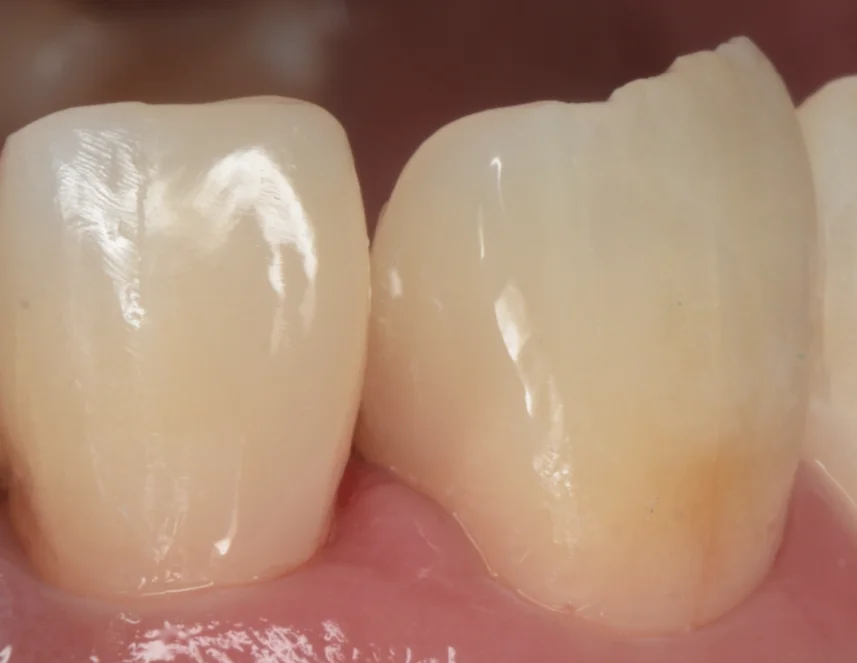

まずは術前からです。

2本の歯の間にレジンでの治療痕があります。

特に左側の適合が悪く、歯茎の上に乗ってしまっている状態になっていますね。

また歯に関しては元々小さい形態だったのも気になると言うことでしたので、このタイミングで治すこととなりました。